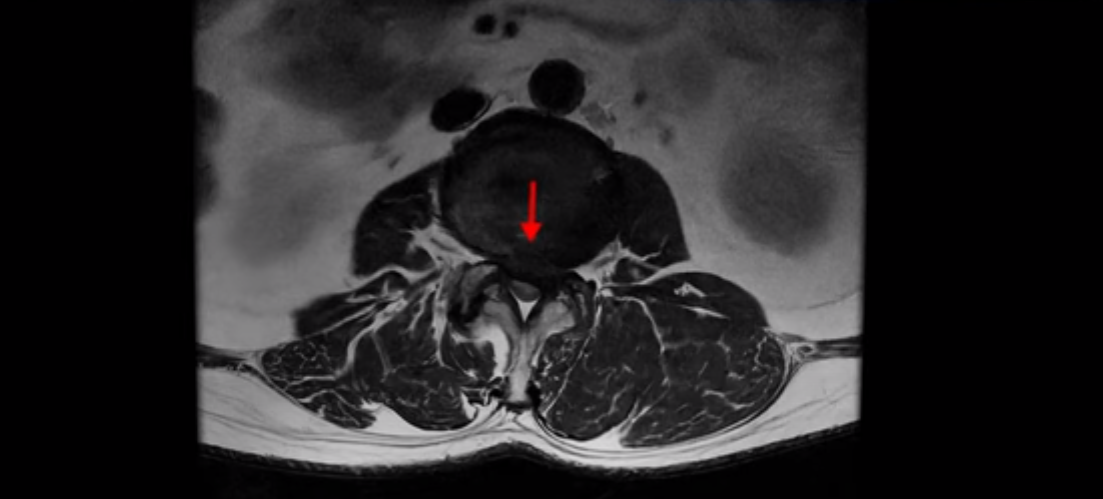

이 환자분은 고관절 쪽이 10년이 넘게 아팠고, 5년 전에는 갑자기 허벅지와 다리가 아파 못 걷게 돼서 허리 수술을 받습니다. 그리고 3년 후에 다시 재발합니다. 고관절 통증은 허리 수술 이후에도 좋아지지 않고 계속 아팠습니다. 수술하고 재발한 이후로 원래부터 아프던 고관절은 물론, 양쪽 엉덩이와 사타구니 및 허벅지가 다 아파서 잘 걷지도 못하고 또 앉거나 누워도 아파서 뒤척거리기도 힘듭니다. 이분 MRI를 보면 여러 마디가 다 안 좋습니다.

2번 3번은 디스크가 심하게 터져있고 협착까지 있습니다.

수술한 부위에 상처 조직이 생겨 유착된 부위가 보입니다. 왼쪽, 오른쪽 신경 가지가 빠져나가는 추간공을 보면 오른쪽도 여러 마디가 좁아져 있고

이렇게 허리 여러 마디와 신경 나가는 구멍 오른쪽, 왼쪽이 다 안 좋으니까 양쪽 엉덩이와 다리가 다 아픈 겁니다.